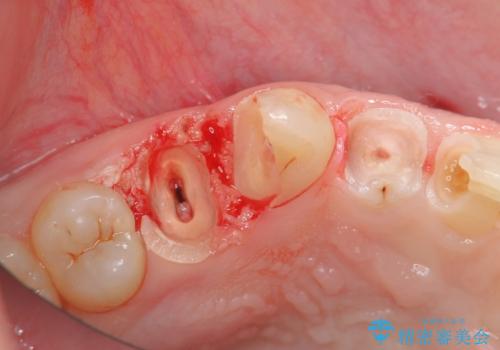

残根状態の歯、神経まで虫歯が達し失活した歯、歯肉縁下まで及んだ虫歯が多数認められます。

まず虫歯を拡大鏡、マイクロスコープ下で丁寧に取り除き歯肉縁下の虫歯を歯周外科により解決したのち、ジルコニアクラウン製作を行っていきます。